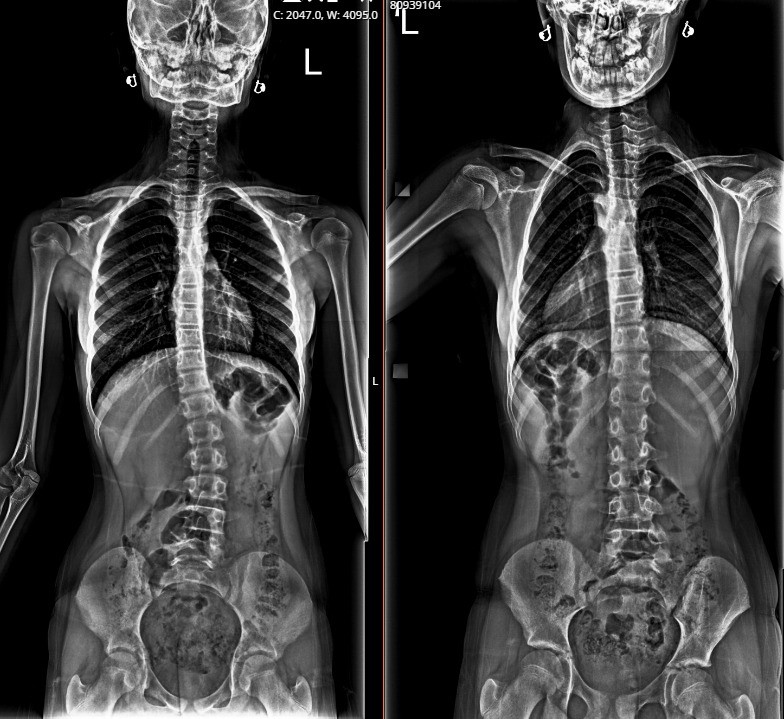

“Melis, bir buçuk yıldır dış hekim tarafından skolyoz takipli, bize kontrole geldi. Değerlendirdiğimiz zaman; 26 derece skolyoz olduğunu tespit ettik, nedenini araştırırken pelvik dengesizlik dediğimiz leğen kemiğinde bir dengesizlik olduğunu değerlendirdik. Yaptığımız klinik değerlendirmeler ve fizik muayene sonucu; bacakta eşitsizliğin dengelendiği zaman, skolyozun fayda görebileceğini öngördük. Yaklaşık 1,5 cm yükseklik ayağına uygulayarak tekrar röntgenini çektiğimizde, skolyoz derecesinin sıfıra yakın bir dereceye indiğini gördük. Sonrasında Melis'e tabanlık verdik, herhangi bir korse ya da cerrahi tedavi olmadan derecesini bu şekilde takip etmeyi düşünüyoruz. Takiplerimizde düzenli aralıklarla yaptığımız değerlendirmelerde ve röntgen kontrollerinde herhangi bir ilerleme olmazsa, süreci bu şekilde tamamlamayı planlıyoruz. Herhangi bir ilerleme veya ekstra bir ihtiyacı olduğunda da yakın takiplerle, gerekirse korse gerekirse fizik tedavi gerekirse de cerrahi olarak müdahale edebiliriz.”